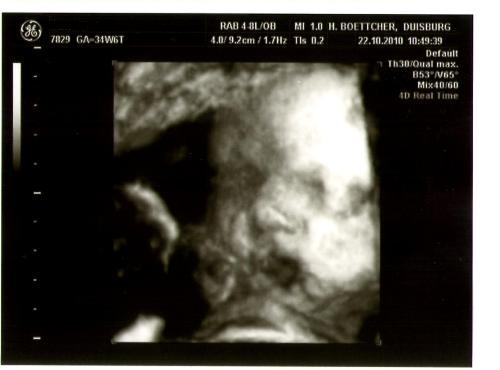

@ me: Der Ultraschall war einfach genial. Unser Krümel hat sich viel bewegt. Die Nackenfaltenmessung war unauffällig. Wir haben jetzt noch einen Bluttest gemacht. Das Ergebnis erhalten wir am Donnerstag. Wenn die Werte auch unauffällig sind, werde ich keine Fruchtwasseruntersuchung machen lassen. Habt ihr bzw. macht ihr eine Fruchtwasseruntersuchung? Wann habt ihr das Utrogest abgesetzt? (Leo, glaub ich nach der 12.SSW) Wurden danach die Blutwerte nochmal kontrolliert?

Baby SSW 12+4.JPG

SSW 12+4.JPG

Tolle Bilder von euren Krümel! :jaja:

@maja: Hej, das sind ja wunderschöne Bildchen:knuddel:!!! Und klasse das bei der Untersuchung alles Bestens war! Ich habe das Utrogest auch bis zur 12. Wochen genommen…bzw. es bis dahin langsam ausschleichen lassen! Die Werte wurden bei mir aber auch nicht überprüft!

@Liebe Maja76: Oh, Du hast auch ein total schönes Bild von Deinem Krümel bekommen :knuddel: Ich denke mal, das Deine Blutwerte in Ordnung sind. Die andere Fragen kann ich Dir leider nicht beantworten auf bekannten Gründen *g* , aber ich denke, die anderen hier können Dir weiterhelfen. Lieb von Dir :knuddel: , es bleibt mir nicht viel übrig als weiterhin positiv gestimmt zu bleiben, andersrum wirds ja auch nicht besser, ne? Ich fand es aber auch schade, kein Wunder zu bekommen.